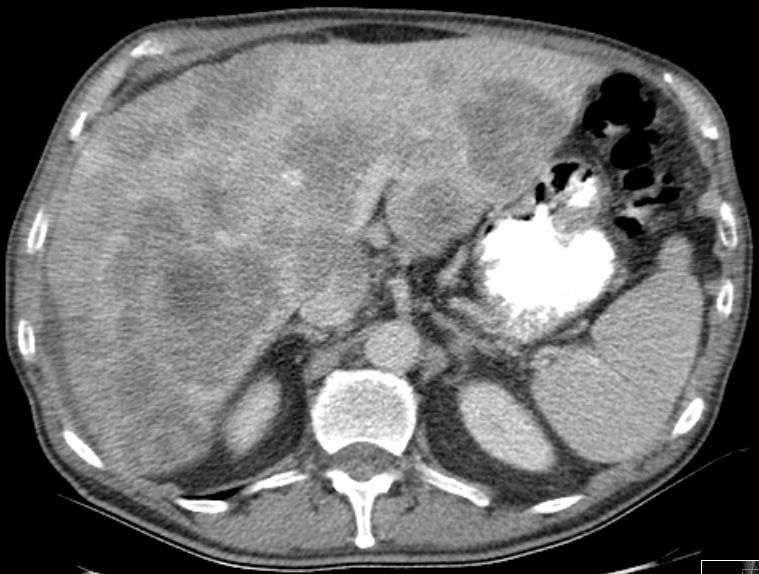

39-jährige Frau mit einem primär hepatisch metastasierten Transversum-Karzinom. Histologisch gering differenziertes Adenokarzinom ras-Wildtyp. Das CT zeigt eine große Metastase im rechten Leberlappen und eine Metastase im Lobus caudatus. Letztere ist schwer zu resezierten und sollte in einem Zentrum operiert werden.